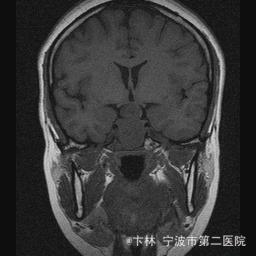

40岁女性,因“双眼视力下降三月余伴停经1个月余”入院。 患者三月前无明显诱因下出现双眼视力下降,视物模糊,尤以左眼为甚,只能近距离看到手动,无头痛、头晕,无恶心、呕吐,无视物旋转,无行走困难等不适,患者曾在某眼科医院就诊治疗,考虑为双眼视神经炎,予以营养,补液对症等治疗(具体不详),情况不见好转,近一月来患者月经停止,来我院神经外科门诊,予以查头颅CT,头颅MRI,提示“垂体大腺瘤”,为求进一步治疗收住入院

予以完善血,尿,粪常规检查,及凝血功能全套,输血功能全套及垂体功能全套,蝶鞍冠状CT等术前检查措施,行经蝶入路垂体瘤切除术。术后予以对症,补液,调节血电解质等治疗,患者视力明显改善,复查头颅MRI提示肿瘤基本全切,一周后患者出院。

此病人颅内垂体瘤体积较大,突破鞍隔压迫视交叉,故患者视力视野障碍为首发症状,该肿瘤主体有大部分向蝶窦腔生长,因此采用经蝶手术入路,肿瘤切除满意,术后患者视力视野恢复满意,。